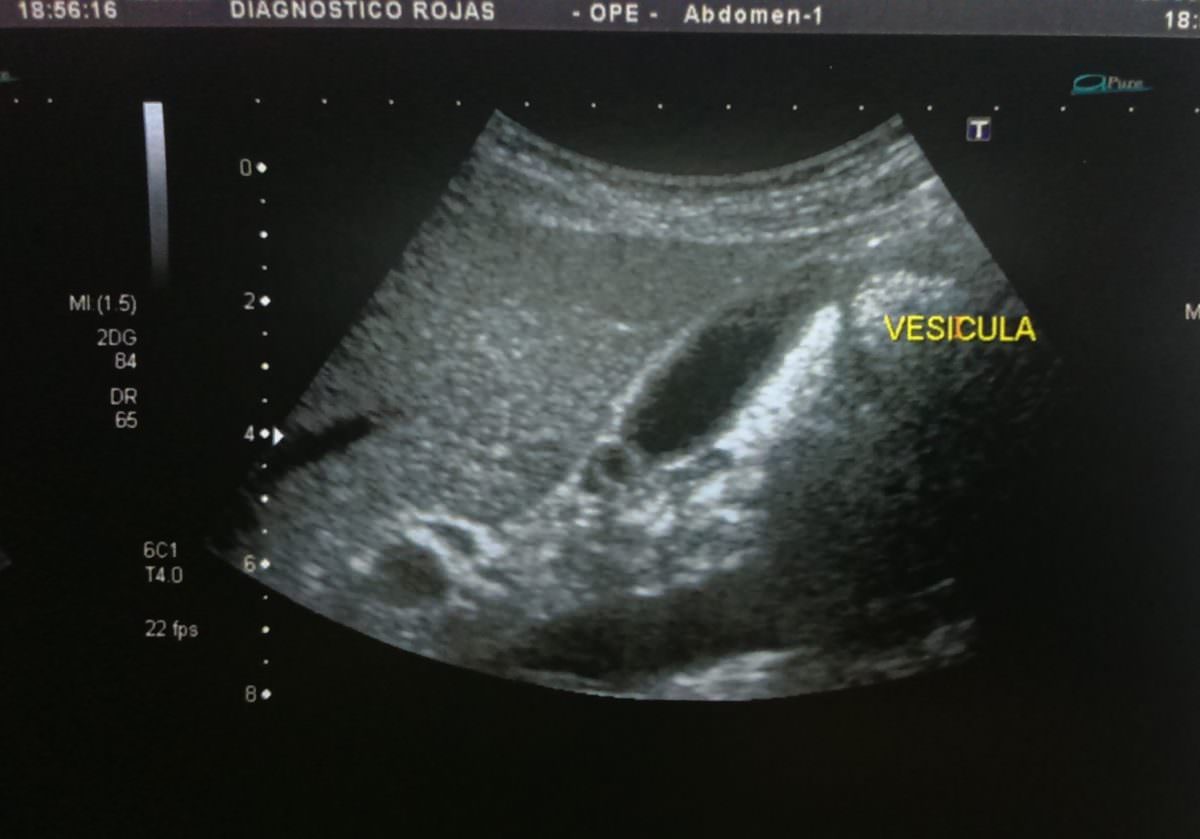

Aplicaciones en obstetricia y ginecología:.

que es una ultrasonografia La ultrasonografía eus ofrece una imagen. La denominación ecografía o ultrasonido se refiere a un procedimiento que emplea ondas sonoras de alta frecuencia para ver el interior del cuerpo, colocando un transductor o. Una ecografía, también conocida como sonograma, es una prueba de diagnóstico por imagen que utiliza ondas sonoras (ultrasonido) para crear imágenes de órganos,. La ultrasonografía es un método de diagnóstico por imagen que utiliza un transductor para emitir. Un ultrasonido de la mama es una técnica de imágenes que se utiliza comúnmente para detectar tumores y otras anomalías en los senos. Aplicaciones en obstetricia y ginecología:. El ultrasonido es un examen médico no invasivo que ayuda a los médicos a diagnosticar y tratar condiciones médicas. Descubre qué es un ultrasonido o ecografía y cuáles son sus usos en el cuidado de la salud.

Prácticas para un Examen de Ultrasonografía